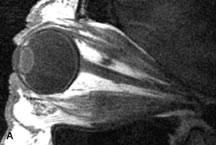

On MRI, uveal melanomas have a typical appearance that helps to differentiate them from other primary and secondary intraocular tumors as well as choroidal detachments. Pigmented melanomas are hyperintense on Tl-weighted images, hypointense on T2-weighted studies, and hyperintense on proton density–weighted examinations (Fig. 24).30,31,50,80–82 These signal characteristics have been attributed to the paramagnetic properties of melanin because of stable free radicals that shorten the T1 and T2 relaxation times. Moderate enhancement is seen on postgadolinium T2-weighted images. Gadolinium-enhanced T1-weighted images are particularly sensitive in detecting choroidal melanomas.83 MRI may be less sensitive in detecting extrascleral extension of tumor than echography performed by an experienced ultrasonographer.84

Fig. 24. A. T1- and (B) T2-weighted MR scans demonstrate a small nodular intraocular mass (arrows) that is very hyperintense on the T1-weighted scan and hypointense on the T2-weighted image. This signal intensity pattern is due to the presence of free radicals within melanin granules. C and D. Postcontrast fat-suppressed T1-weighted scans demonstrate homogeneous intense enhancement of the lesion and no evidence of seleral penetration or optic nerve invasion.